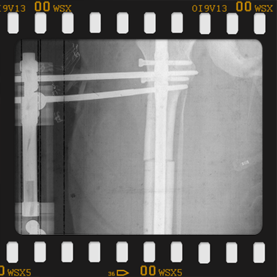

Görüntüleri büyütmek için üzerine tıklayınız.

Görseli büyütmek için üzerine tıklayınız. Görseli büyütmek için üzerine tıklayınız. Radyografi görseli büyütmek için üzerine tıklayınız. Radyografi görseli büyütmek için üzerine tıklayınız. Radyografi görseli büyütmek için üzerine tıklayınız.